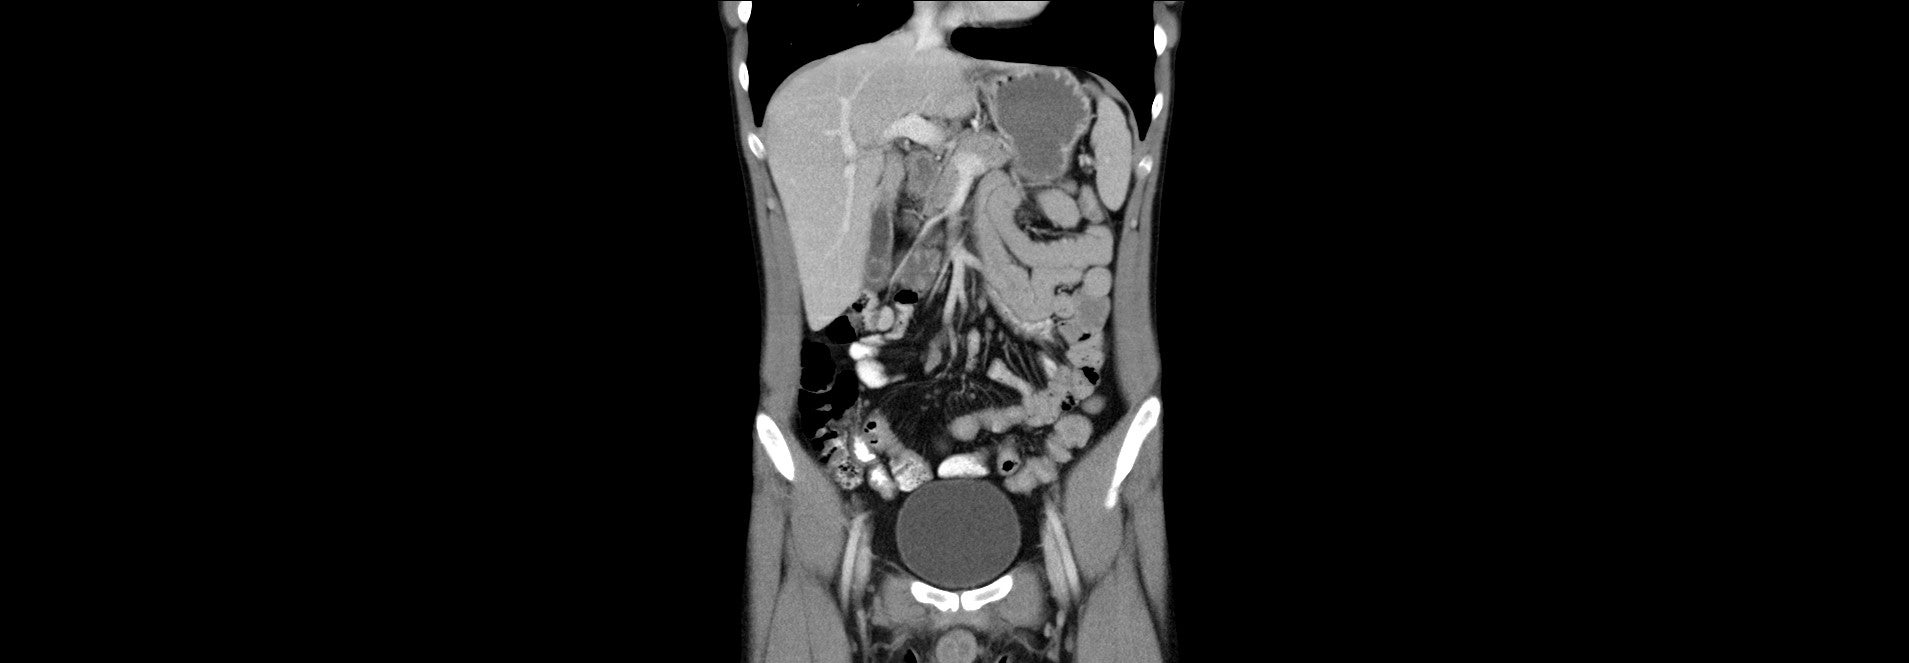

Zobrazovací metody:

CT břicha ze dne 28.02.2023

Klinika radiologie a nukleární medicíny FN Brno